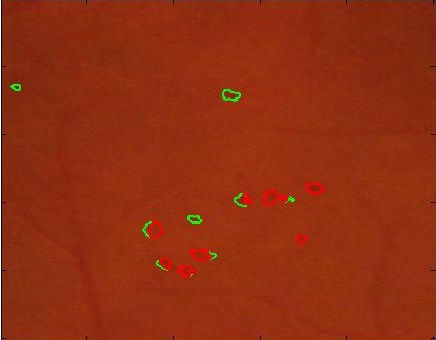

Figure 5 shows results of MA segmentation using the images generated by different super resolution methods. Figure 5 (a) shows the original full sized image with the regions having majority of the MAs outlined by a red square. Figure 5 (b) shows the cropped image region with yellow arrows identifying location of MAs. Figure 5 (c) shows manually drawn contours around the MAs. Figure 5 (d) shows the segmentation results obtained using the original HR images as part of the training and test set. The ground truth manual contours are shown in green while the segmentations obtained using the U-Net algorithm is shown in red. The performance on the HR images is an indication of the minimum error (or best possible segmentation performance). Figures 5 (e)-(h) show, respectively, the super resolved images obtained by , , and along with the super imposed segmentation results. It is quite obvious that the results obtained using are the best. It is interesting to note that the SR images obtained using and lead to blurred edges of the blood vessels and MAs, although in the case of the SR images are not blurred. The other two methods, and result in such poor quality images that the MAs are not even detected for this particular example.

![]() |

| (a) | (b) | (c) | (d) |

| (e) | (f) | (g) | (h) |